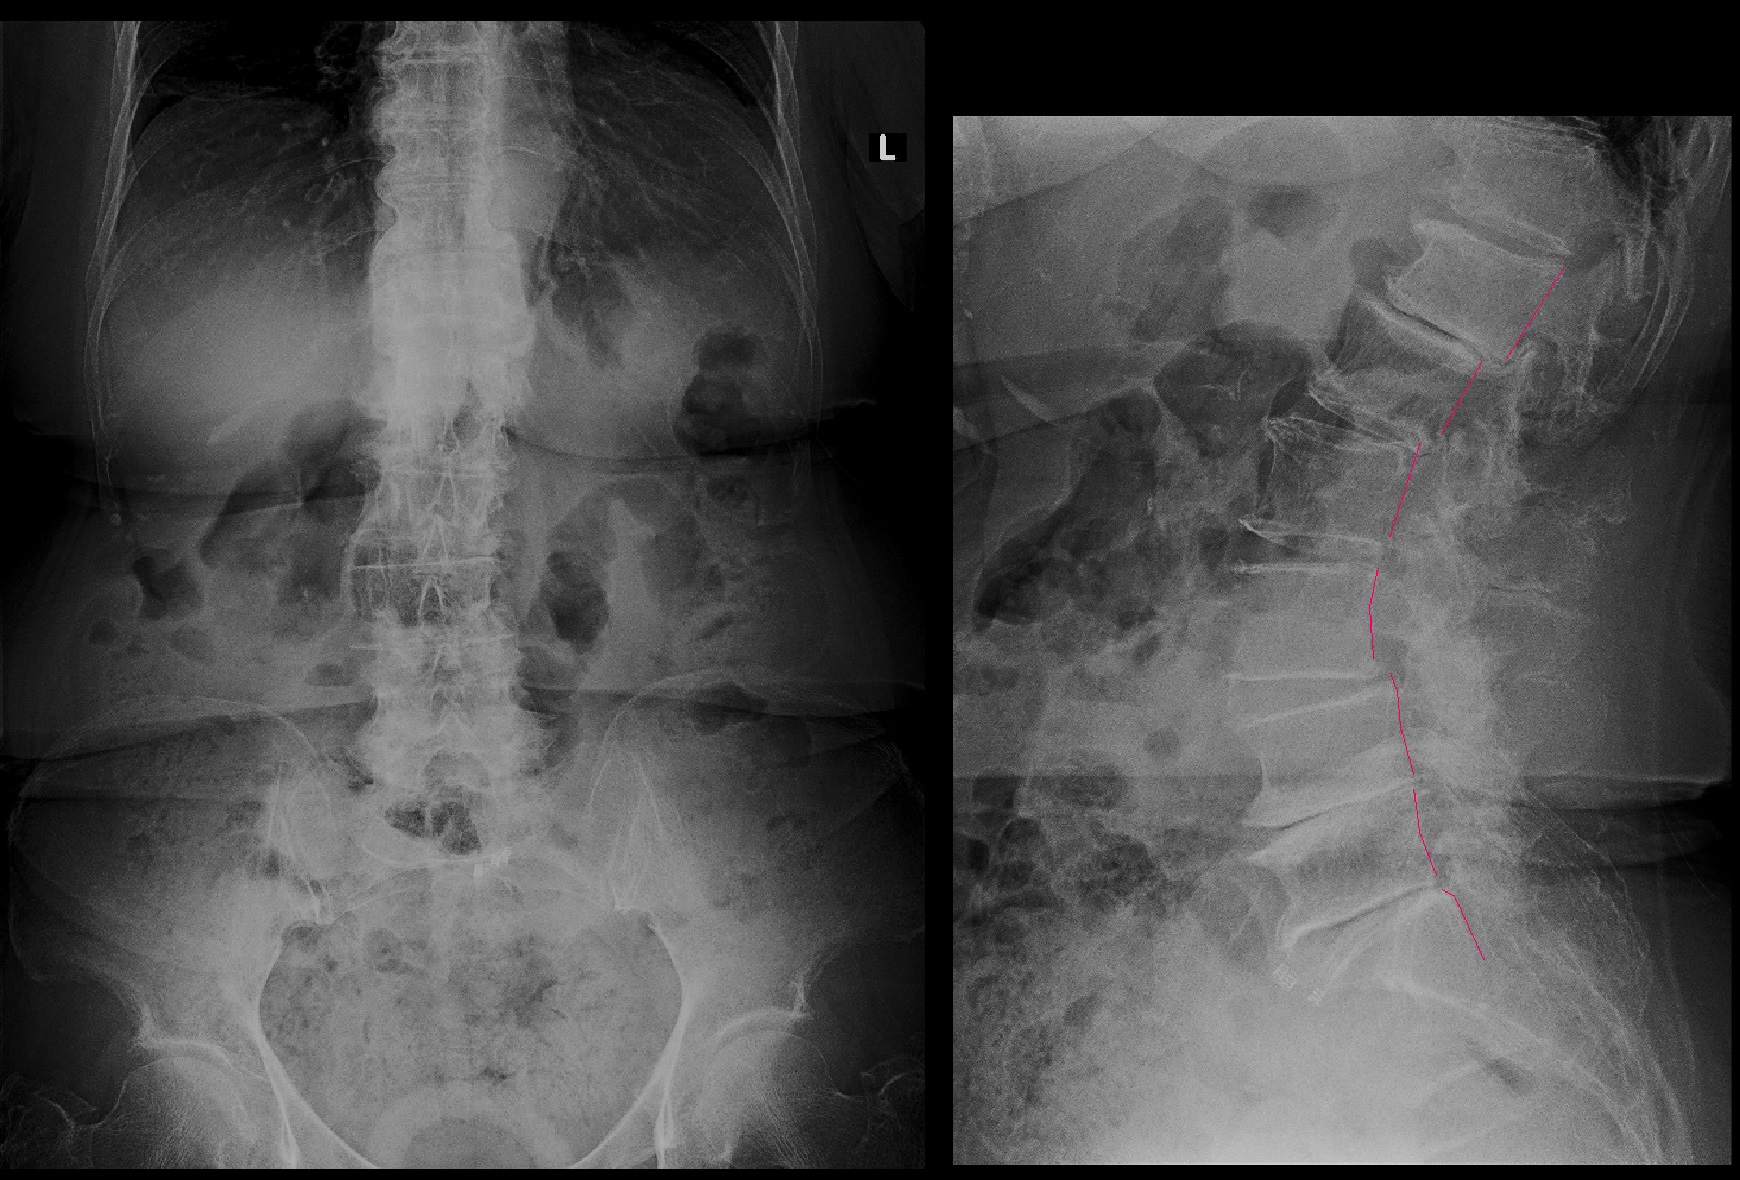

腰椎Xp.jpg

腰椎のレントゲンは年齢相応か、さほど老化現象はひどくないというものでした。

RB.jpg

8月23日にはVAS4~5の腰痛はVAS2に軽減し、ほとんど気にならないという評価となりました。

20年間諦めていた腰痛は実は改善の治療方法があったということだと私には思われます。